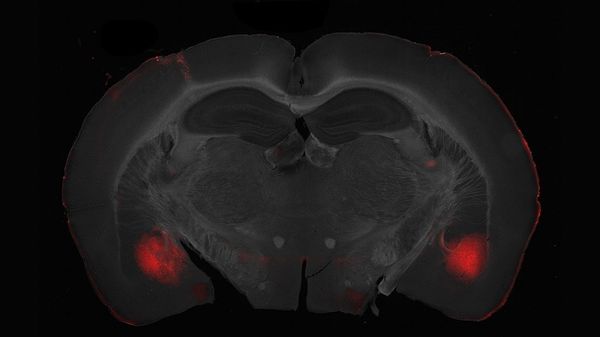

Egoista o altruista: a modulare il comportamento verso gli altri è un circuito nervoso del cervello che collega il centro delle emozioni , ovvero l'amigdala baso laterale, con la regione delle decisioni , la corteccia prefrontale. Lo dimostra uno studio …